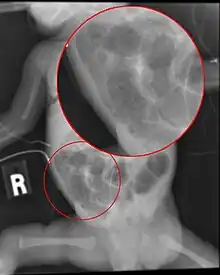

Diagnosis is usually suspected clinically, but often requires the aid of diagnostic imaging, most commonly radiography, which can show the intestines and may show areas with death tissue or a bowel perforation.[18] Specific radiographic signs of NEC are associated with specific Bell's stages of the disease:[19]

- Specific radiologic signs (pneumatosis intestinalis or portal venous gas)

- Severe radiologic signs (pneumoperitoneum)

Alimentary tract of infant showing intestinal necrosis, pneumatosis intestinalis, and perforation site (arrow) (autopsy)

Close-up of intestine of infant showing necrosis and pneumatosis intestinalis (autopsy)